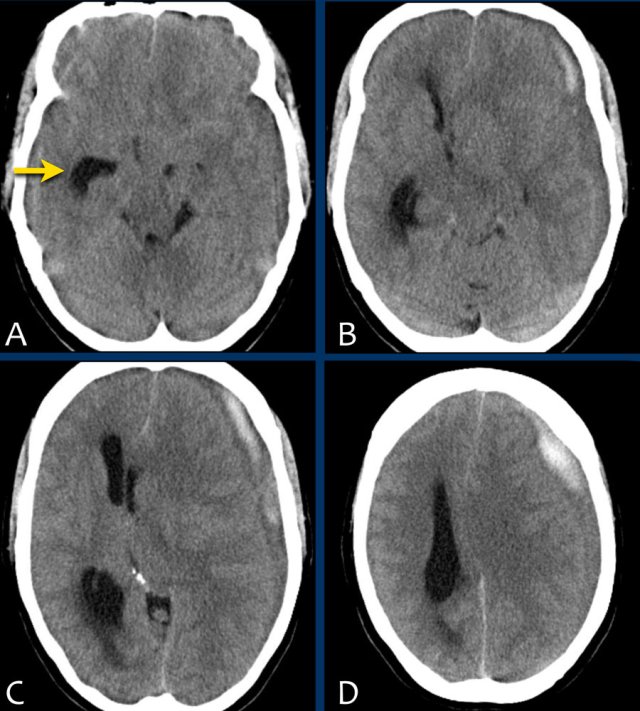

Duret hemorrhage

A 54-year-old man, who was treated with anticoagulants after aortic valve replacement, developed severe headache after being hit  by a ball.

The following day his condition worsened with loss  of consciousness, respiratory distress and a non-reactive dilated left pupil.

The initial CT of his head showed an acute subdural hemorrhage along the left convexity with subfalcine and uncal herniation. The hemorrhage was evacuated surgically.

Postoperatively the CT showed an acute bleeding within the brainstem, which had a lethal outcome.

This brain stem hemorrhage is called a Duret hemorrhage.

They are small linear areas of bleeding in the midbrain and upper pons of the brainstem caused by a traumatic downward displacement of the brainstem with parahippocampal gyrus herniation through the tentorial hiatus.